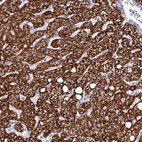

Immunohistochemical staining of human liver shows strong granular cytoplasmic positivity in hepatocytes.